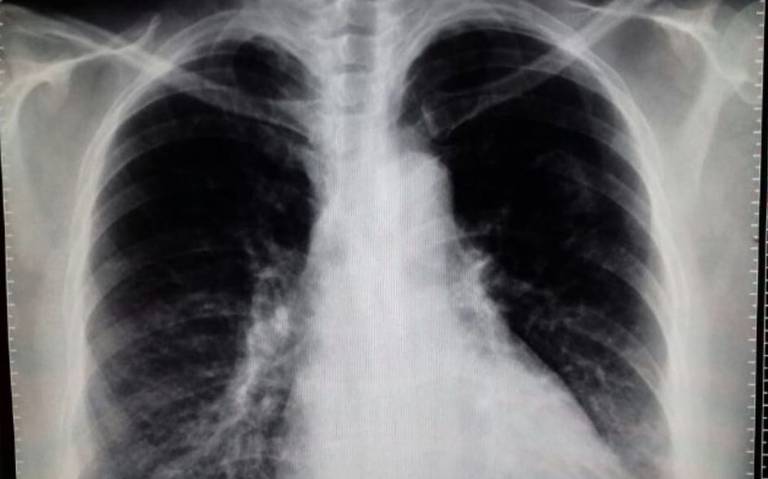

Asociación entre antidepresivos con neumonía y exacerbación en pacientes con EPOC: una serie de casos autocontrolados

Los antidepresivos se asociaron con un mayor riesgo tanto de neumonía como de exacerbación en pacientes con EPOC, disminuyendo los riesgos al suspender el tratamiento. Estos hallazgos sugieren una estrecha vigilancia de los efectos secundarios de la prescripción de antidepresivos y la consideración de intervenciones no farmacológicas. Thorax, 19 de junio de 2023